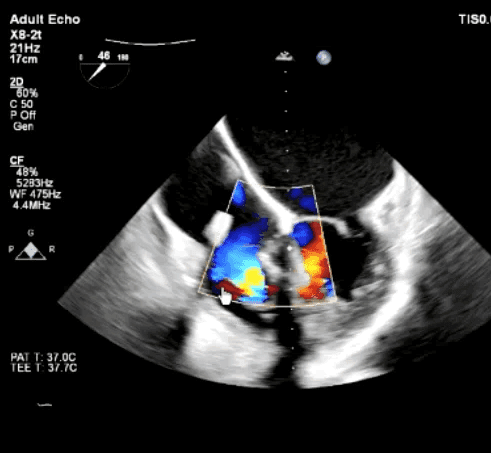

术前心超评估

三尖瓣极重度反流,且在前瓣和隔瓣处有3枚TriClip,并在3个TriClip中间有中度的固有反流。经过评估,本次K-Clip™手术的缩环位点于后瓣中点,预期对患者的极重度的三尖瓣反流进行改善。

术后超声

显示三尖瓣中度反流,反流仅来源于TriClip前隔瓣处的固有反流。患者的三尖瓣反流获得了明显改善。